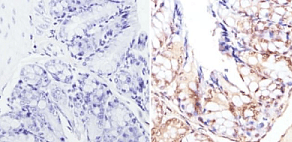

Rabbit Polyclonal CREBBP antibody. Suitable for WB, IHC-P, ICC/IF and reacts with Human, Mouse samples. Cited in 58 publications. Immunogen corresponding to Synthetic Peptide within Human CREBBP aa 150-200.

Applications ICC/IF, IHC-P, WB